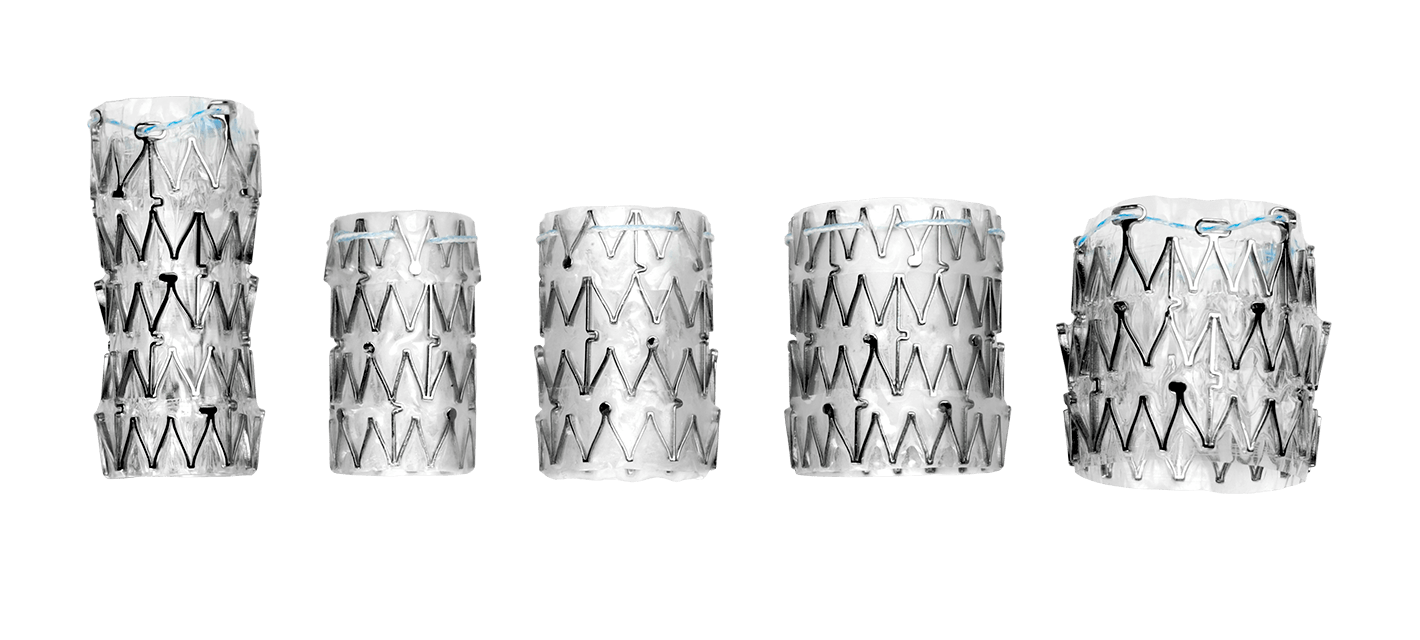

AORTIC ANEURYSM

The aorta runs from the heart through the center of the chest and abdomen. It’s the main blood vessel that brings blood to the abdomen, pelvis, and legs. An abdominal aortic aneurysm (AAA) is a life-threatening condition that occurs when the vessel enlarges, putting it at risk of bursting. Men are 4-15 times more likely to develop an AAA than women

Learn more about AAA. To learn more about our packs, wires, and other cardiac products, please visit our Merit Vascular page.

MERIT PRODUCTS